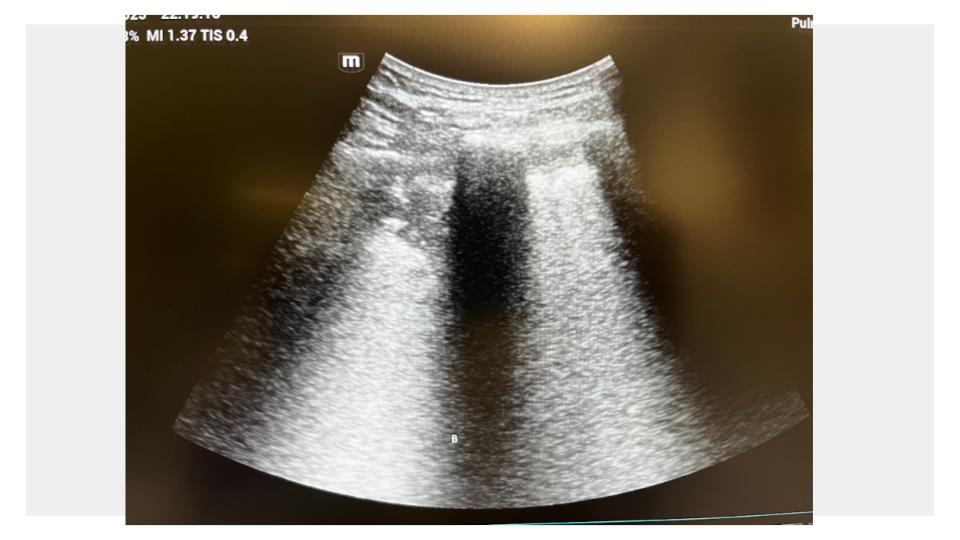

Se realiza ecografía pulmonar a pie de cama, donde se objetiva: consolidación subpleural en lóbulo inferior derecho, compatible con neumonía.

Se inicia tratamiento antibiótico dirigido por sospecha de neumonía neumocócica de la comunidad, sin necesidad de hacer otras pruebas diagnósticas que irradian o de derivar al hospital. Diagnóstico y tratamiento precoz en patología incipiente que puede tener evolución rápida y tórpida